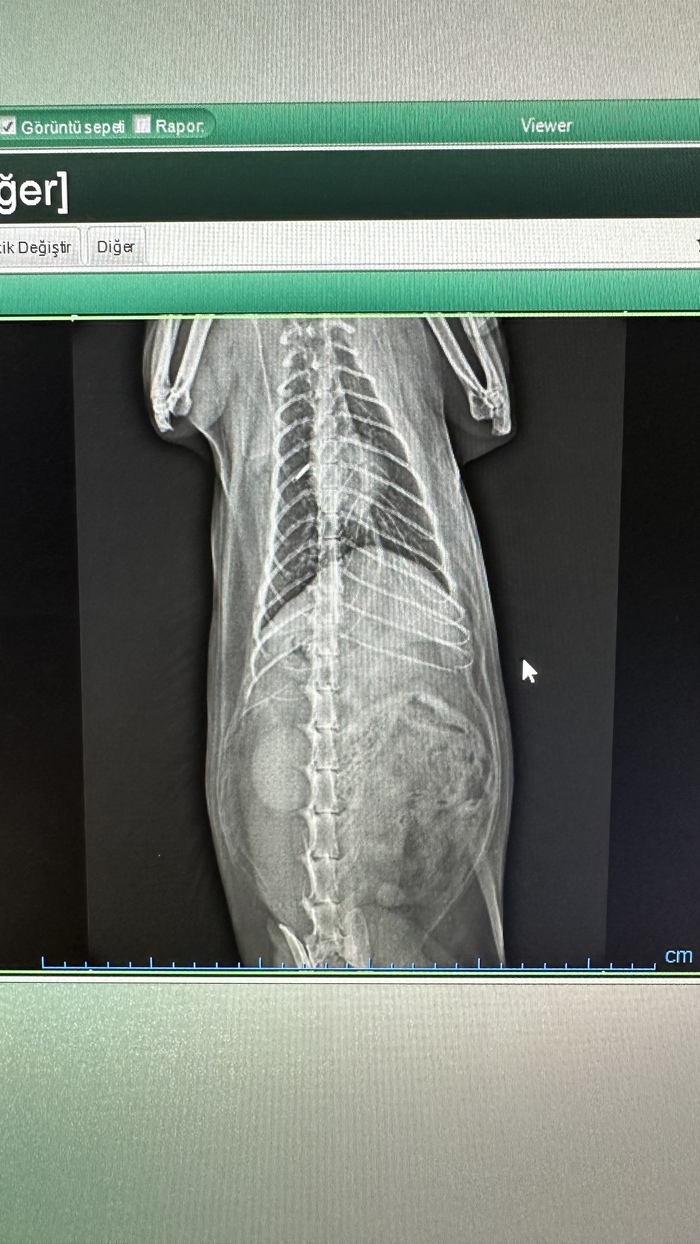

Потеряв надежду вылечить кота посредством ветеринаров, обращаюсь к сообществу. Дело в следующем: в январе месяце у кота, на коже нижней части живота, образовался небольшой, в пару миллиметров, свищ, из которого сочилась жидкость, по типу сукровицы. Объективно: кожа живота отечная, но, так как у этой породы курдюк и очень длинная шерсть, этого видно не было, пока не побрили живот, Кот домашний, на улицу не ходит, привитой, 7 лет, мейнкун, без хронических болезней. Уже на следующий день, повезла его к ветеринару, который назначил антибиотик форсеф на 10 дней и обработку ранки хлоргексидином. В ходе лечения, этот свищ затянулся, но тут же открылся другой, выделения продолжаются, без запаха, на ощупь липкие, как сукровица. По пути его передвижений по квартире, на полу, диванах видны кляксы. Повторно едем к ветеринару. Там ему дают наркоз, проводят ревизию свища, ставят диагноз "лимфаэкстравазат" делают очень тугую перевязку живота, назначают амоксициллин. Проходит ещё две недели. Перевязывают его каждый день. Кот ест хорошо, пьет, испражнения в норме. На 15-й день, ветеринар говорит, что ничего не может больше сделать, у кота сильнейший лимфостаз на задних лапах, хвосте и яичках. Едем в ветклинику другого государства. Там сначала назначают стероиды, затем делают все анализы, УЗИ сердца (все в норме) берут на операцию. После операции, результата особо нет, течет теперь уже из дренажей, по бакпосеву синегнойка, кишечная палочка и клебсиела. Из-за того, что его туго бинтовали 2 недели, эта жидкость не выходила наружу, а скапливалась внутри, под кожей. Из-за воспаления у кота расплавилась подкожка, все стало переходить на бедра. Кот 10 дней на стационаре в клинике, по анализам все в норме, но диагноза, как и прежде нет, как и эффекта от лечения. В итоге 23 дня Амикацина, 10 дней ципрофлоксацина, промывание дренажей бактериофагом... Результата ноль. Кот сейчас дома. Из кота течет. Кот ест, пьет, нормально ходит в туалет. Но продолжаться это не может долго, по моему мнению. Через неделю ровно три месяца он в таком состоянии. Если у кого-то были такие случаи, напишите мне, пожалуйста! Я не могу потерять его, это мой меховой сын. Прикладываю фото... Может, для кого-то они будут информативны...